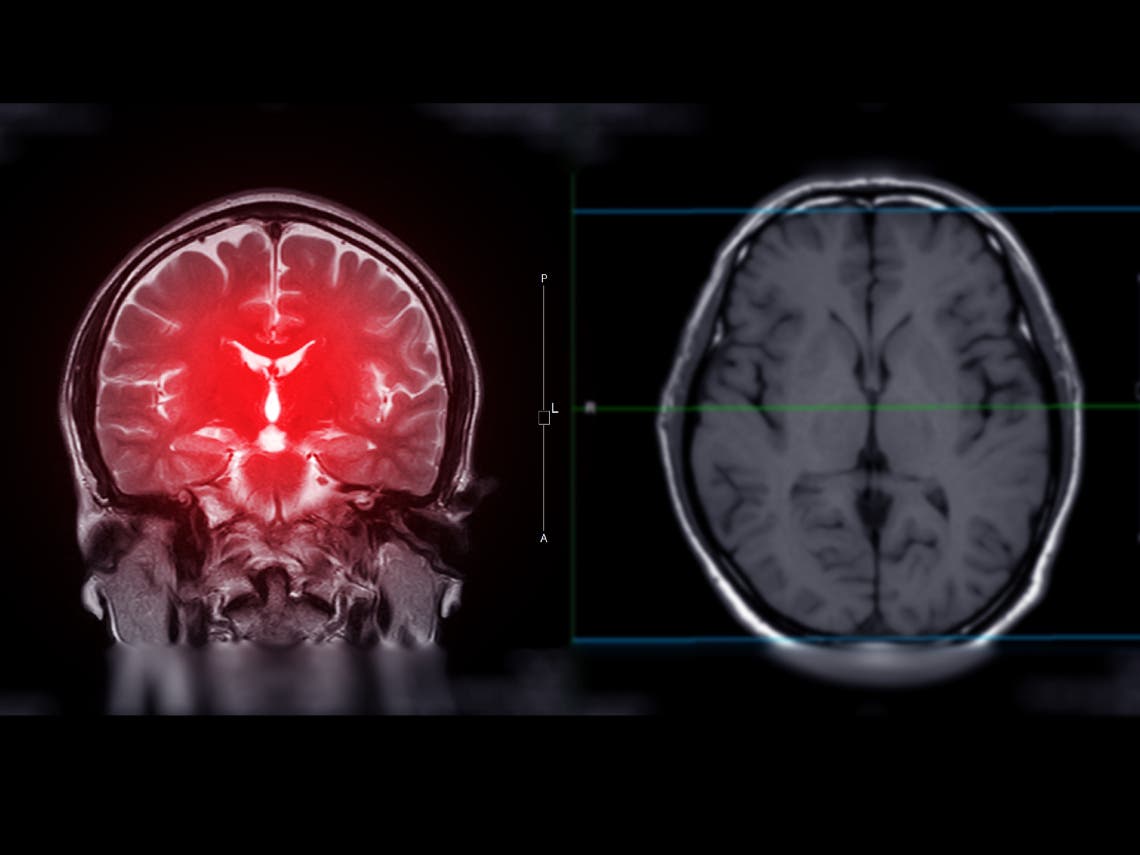

The bank will study the of long-term effects of contact sports on the brains of athletes. Exposure to concussions or mild or traumatic brain injury has been found to increase the chances of developing cognitive and psychiatric syndromes, as well as the neurodegenerative disease chronic traumatic encephalopathy, later in life.

The brain bank will annually evaluate participants during their lives and perform detailed neuropathological examinations of their brains after death, looking for evidence of chronic traumatic encephalopathy, Alzheimer’s disease, ALS and other neurodegenerative diseases.